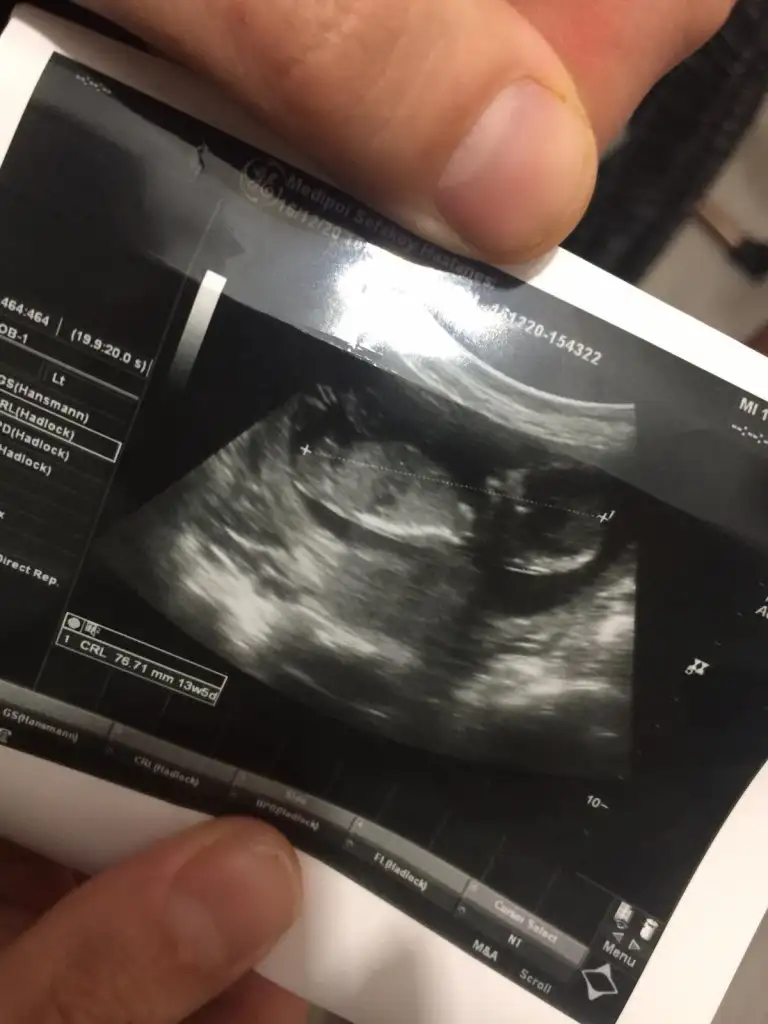

Seninkini at bakayım birde ben göreyim 🤭 ben aslında 12. Haftada gittiğimde kız olduğunu fark ettim pipi gibi birşey yoktu assagi doğru eyik gözükuyordu🤗

Bizimkide bu su pipi mi kordon mu anlamadım 😅 insallah kordondur yeni oluşan pipi bu kadar büyük olur mu acaba 😅

• IMG-20201216-WA0004.webp

IMG-20201216-WA0004.webp

25,8 KB · Görüntüleme: 56